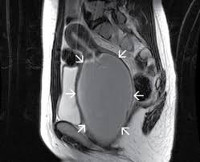

N89.7 Гематокольпос